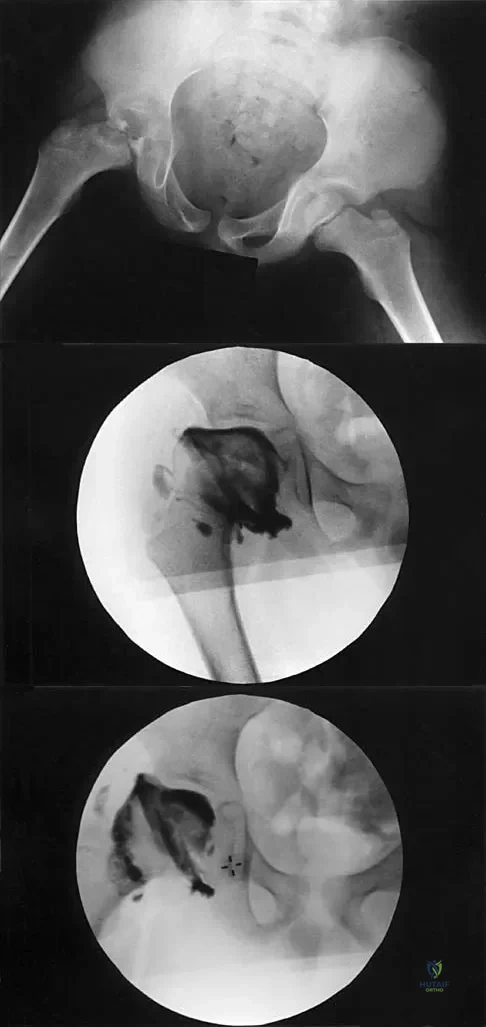

A 7-year-old patient has had a painless limp for several months. Examination reveals pain and spasm with internal rotation, and abduction is limited to 10 degrees on the involved side. Management consists of 1 week of bed rest and traction, followed by an arthrogram. A maximum abduction/internal rotation view is shown in Figure 40a, and abduction and adduction views are shown in Figures 40b and 40c. The studies are most consistent with